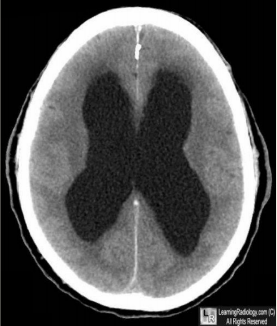

8

Q

What is this?

A

Hydrocephalus Ex-Vacuo

9

Why would a patient with hydrocephalus ex-vacuo have enlarged cerebral ventricles and subarachnoid spaces?

More CSF to make up for loss of brain matter (atrophy, schizophrenia, traumatic brain injury) => maintain ICP